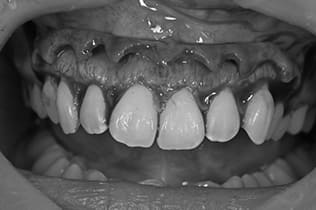

Case01

- 原因

- ガミースマイル

- 治療回数

- 1回

- 治療期間

- 術後治癒も含めて約1か月

- 治療内容

- ガミースマイル改善治療

- 治療費用

- 121,000円

(1ブロックあたり、6前歯部分)

笑った時に歯茎が見えてしまうガミースマイルを改善したいとのことでご来院された患者様です。術後も大変満足していただきました。